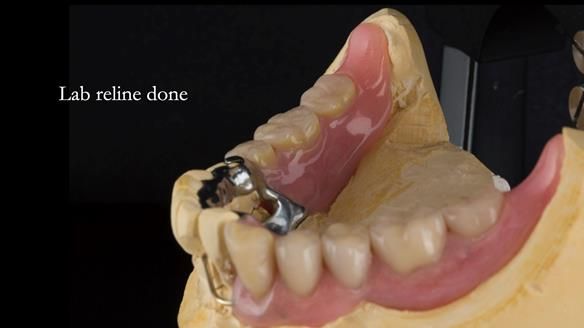

- a good approach to relining distal extension RPDs, similar in principle to the altered cast technique

Instead, we made a Scandinavian-style, metal-based lower RPD.

It was made promptly, then relined gradually over the following year

to optimise fit, comfort, and support.

A reflective note on the lower denture

It’s worth saying that the lower denture in this case was made in the early days of Rowan and me using the Scandinavian approach. Rowan cast the metalwork himself for this denture.

Looking back, we would make this denture more hygienic now. The design and finish would be more refined and delicate, particularly when compared with the upper metalwork, which was made later using Chris Hesketh’s chrome work. I will discuss this in detail at the study club.

That said, the lower denture worked beautifully. It did exactly what it was meant to do, even though, by today’s standards, it looks a little agricultural.